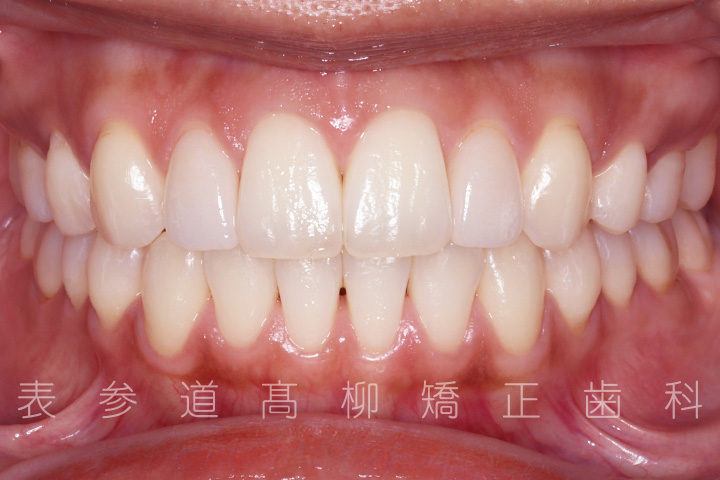

上の前歯が出ているのと前歯が小さいことをお悩みの患者様の症例をご紹介いたします。

治療前→治療後

・矯正治療終了後 加部歯科医院(https://kabe-dent.net) にて2⏊2補綴処置を行った

術前術後の比較